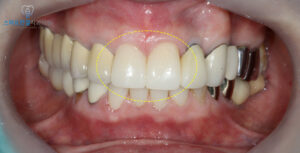

먼저 치아를 다듬어

크라운이 안착될 수 있도록

형태를 준비했어요.

이 과정에서 치아의 축과

교합 상태를 세밀하게 조정하여

이후 보철물이 자연스럽게

들어갈 수 있도록 했어요.

앞니는 심미적으로 가장

눈에 잘 띄는 부위이기 때문에,

치료 기간 동안 불편함이 없도록

임시치아를 먼저 제작하여 장착해 드렸으며,

임시치아의 형태를 통해 최종 보철물의

형태도 미리 확인하고 조정할 수 있었어요.

이를 통해 환자분이 원하시는

심미적 요구와 기능적 편안함을

사전에 반영하여 최종 크라운 제작 과정에

더욱 정밀하게 반영할 수 있었어요.